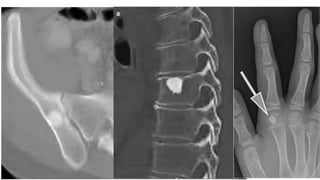

Benign tumor arising from fat -

Intraosseous Lipoma

• Extremely rare

• • Age

• • Wide range = 5-85 years

• • Usually detected in 4th-5th decades

• • L o c a t i o n

• • Lower limb = 75% ( metaphysis)

• • Calcaneum>femur >tibia>fibula

• • Upper limb

• • Skull and mandible

• • Spine & pelvis

• • Ribs

Plain radiograph feature

• Expansile radiolucent lesion with sharply defined

• sclerotic margin

• • No periosteal new bone formation

• Within calcaneum, lipoma has characteristic

• appearance, osteolytic lesion with a central focus

• o f o s s i fi c a t i o n

• CT & MRI

• • Can be homogenous fat content

• • Fatty lesion with central necroses, central

• calcifications o r o s s i fi c a t i o n s

• • Fatty lesion with multiple central necroses, central

• calcifications or ossifications

Differentials for intraosseous lipoma - SBC and Bone infarct